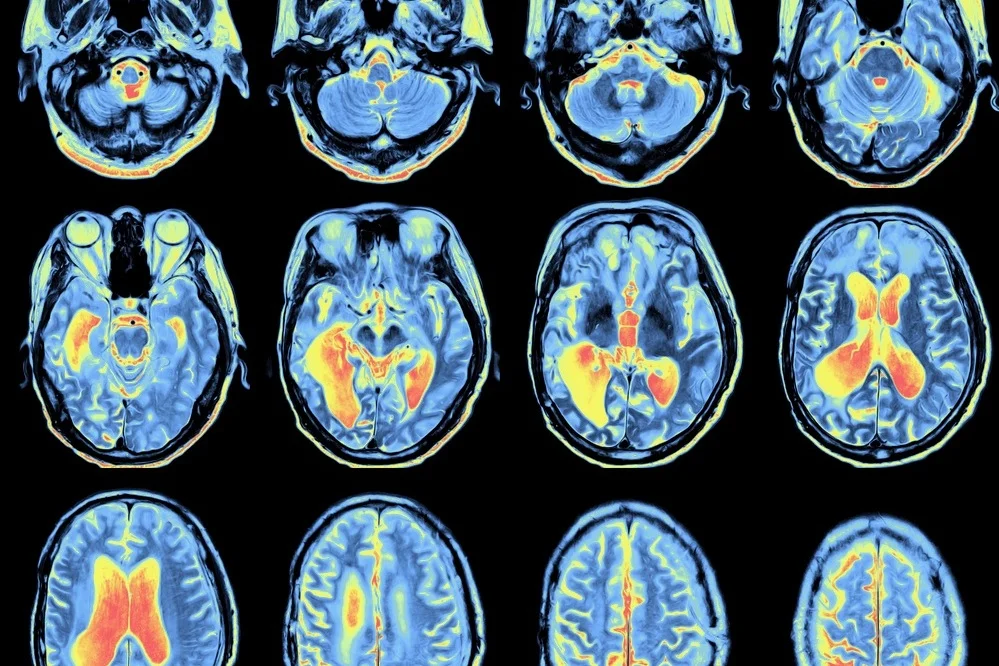

MAGNETIC RESONANCE IMAGING

Functional magnetic resonance imaging (fMRI) is a non-invasive brain imaging technique commonly used by clinicians and neuroscientists to answer questions about the functions of the brain. fMRI can look at the structure and functioning of the brain without needing to inject a test substance or dye. The images obtained can be used to make inferences about brain activity when a task is carried out or when the brain is ‘at rest’. Oftentimes, a research participant is trained to carry out an experimental task (e.g., tapping their fingers, squeezing a ball while he/she is inside the MRI scanner). This is because the task is aimed at activating a set of brain regions or circuits that are revealed after elaborate image pre-processing steps to transform the brain scans into real images (also known as activation images).

Structural MRI takes pictures in a series of time to allow clinicians and researchers to non-invasively look at gross anatomical structures in the brain. They can spatially differentiate types of tissues at high resolution.